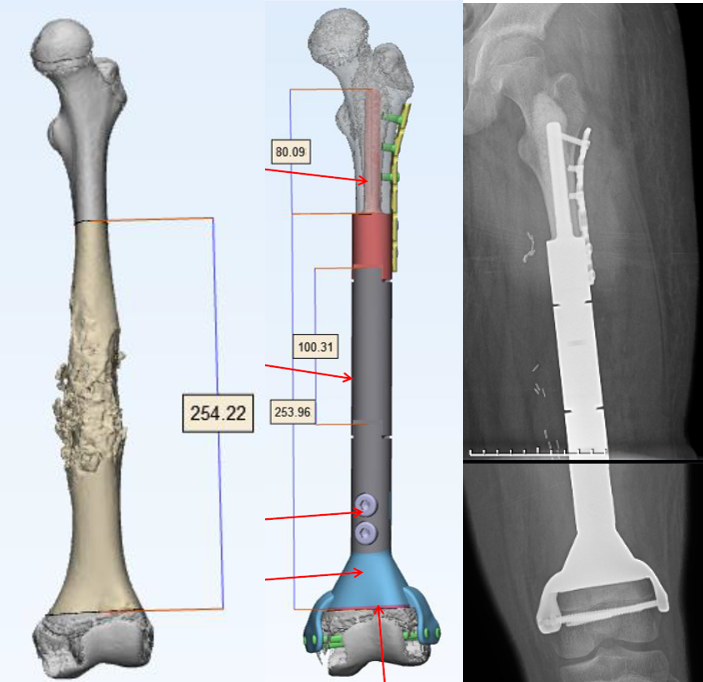

2.手术方案:肿瘤广泛切除+保留骨骺人工假体重建

• 选择3D打印保留骨骺的假体适应生长发育需求

• 定制3D打印假体(远端采用骨长入界面,保留了骨骺,并且保证了远期的骨长入及远期的假体稳定性)